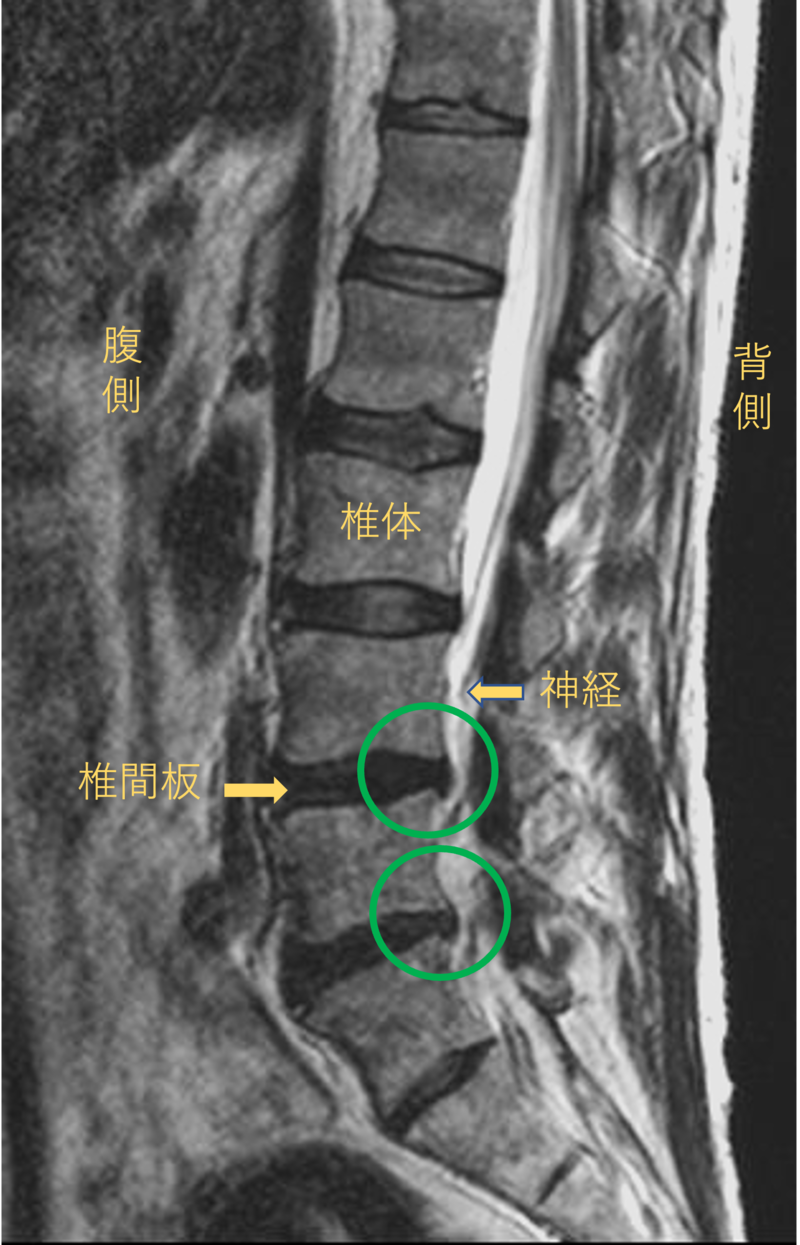

腰を横から見たMRI画像です。

腰椎という骨と骨の間に椎間板と呼ばれるクッションがあります。

このクッションの中身が飛び出す状態が椎間板ヘルニアと呼ばれます。

このMRI画像では、椎間板が背中側に飛び出して神経が圧迫されることが痛みの原因となっておりました。